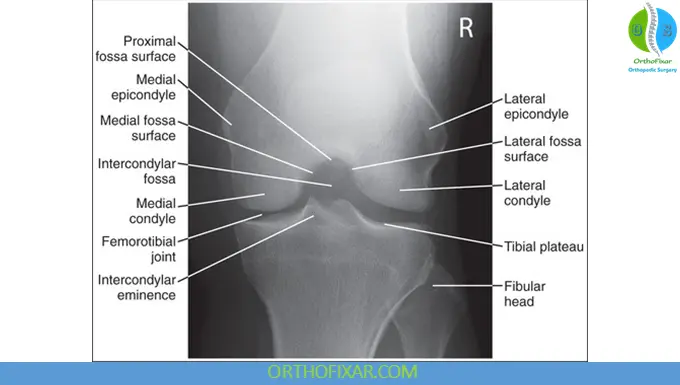

Intercondylar Notch (Tunnel) View

This view evaluates:

- Tibial spine and cruciate ligament attachments

- Intercondylar notch width (notably narrower in some individuals, especially women)

- Osteochondritis dissecans (OCD)

- Loose bodies and subluxation

A reduced notch width may increase the risk of anterior cruciate ligament injury.